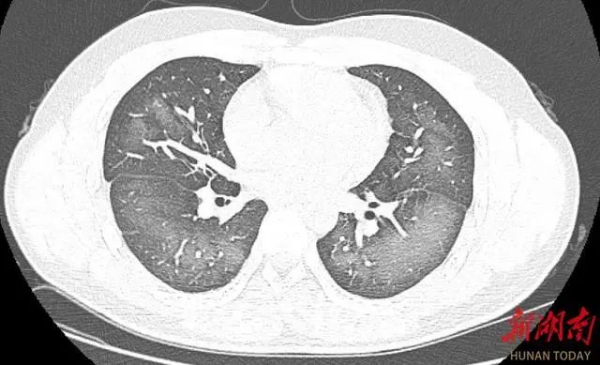

经检查,肺部CT片显示,李林双肺赫然呈现大范围白色样病变,报告提示“白肺”。

“白肺”:一般是指重症肺炎在X线或CT检查下的表现,患者肺部呈现一大片的白色状态,往往会出现呼吸困难、呼吸衰竭,严重者还会出现其他脏器功能障碍。

长沙市第三医院放射影像科的接诊医师表示,除了感染、弥漫性肺泡出血综合征等“白肺”最常见的病因外,吸入有害物质如粉尘、喷雾等,也可导致肺部出现大范围白色样病变。这位年轻的患者就是因为使用不当,吸入了一部分防晒产品进入肺部,导致“白肺”的发生。急诊医生给予吸氧、化痰、抗感染等相关治疗后,李林症状得到明显改善。